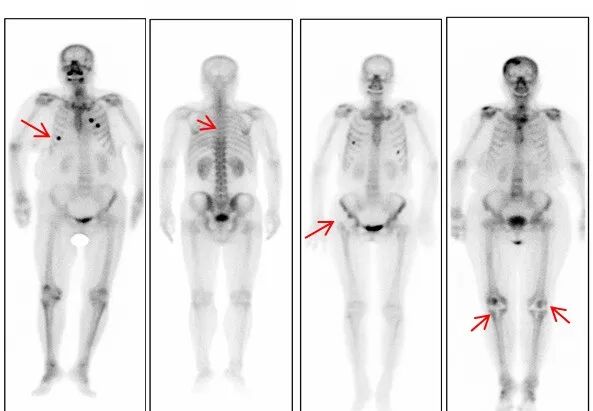

随着医学的发展,骨扫描已成为主要检查项目之一。尤其在恶性肿瘤骨转移的筛查中发挥着不可替代的作用。

全身骨显像又称为骨扫描,全身骨显像是将放射性核素标记的显像剂(如99mTc-MDP)注射到体内,通过离子交换、化学吸附和与骨的有机成分结合的方式沉积到骨骼中,2-3小时后利用单光子发射型计算机断层扫描仪(SPECT)得到显像剂在全身骨骼沉积后的分布情况,从而得到全身骨骼的图像。

一次成像可以了解全身骨骼的情况,对于一些容易发生骨转移的肿瘤如前列腺癌、乳腺癌、肺癌、甲状腺癌等患者治疗前的分期和治疗后的随访具有极为重要的价值;全身骨显像还可鉴别不明原因的骨痛,发现隐匿性骨折,观察移植骨的存活情况及人工关节置换术后的随访。因此,优质的骨扫描影像,能够帮助医生精确诊断病情,而精准影像的获取,除了医务人员规范操作,更需要您的配合。